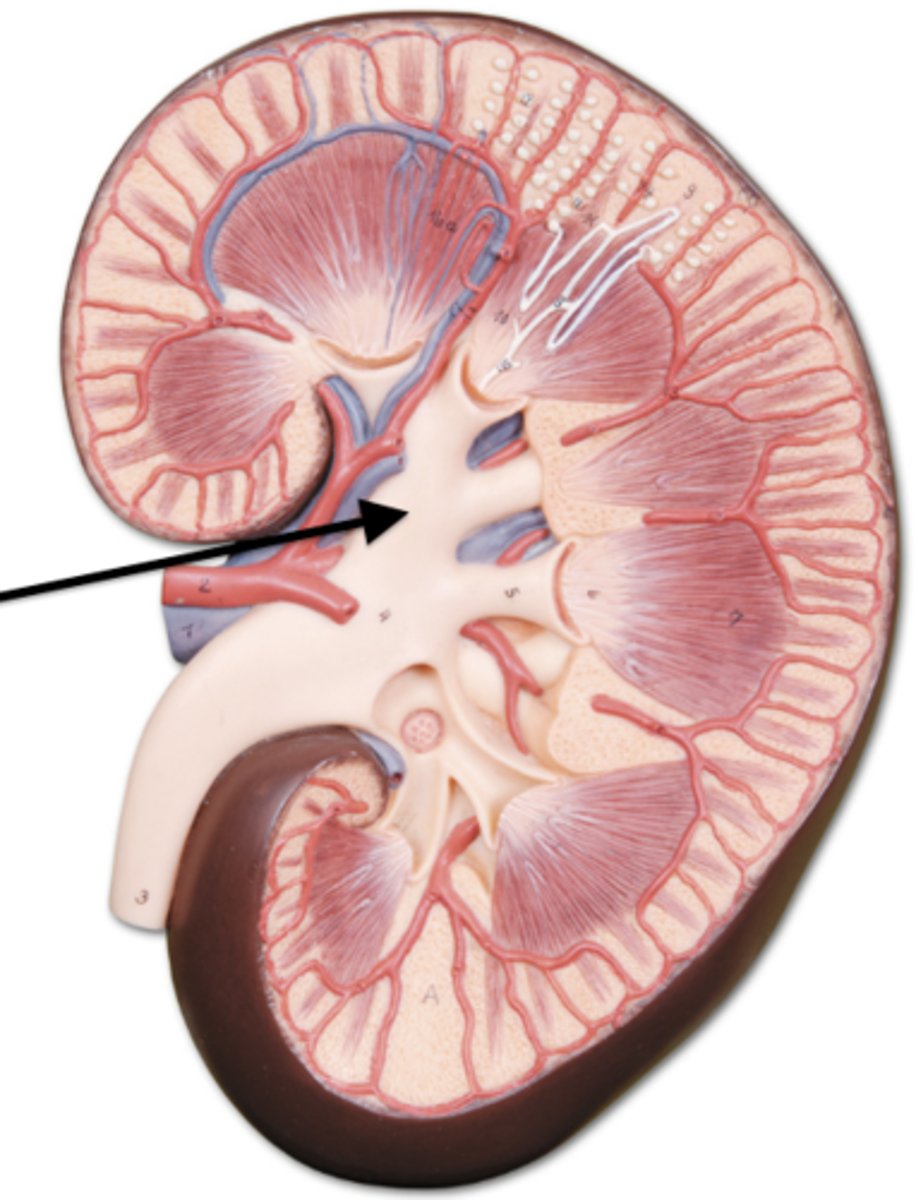

adrenal gland

adrenal gland

arrow

kidney

renal artery

renal vein